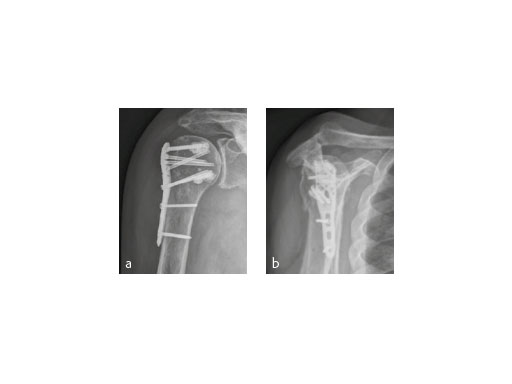

The X-ray review at 3 months after surgery showed an anatomic reduction of the fracture, nicely formatted augmentation, no secondary loss of reduction, and range of motion of the arm reaching the horizontal plane (Fig 7).

A 91-year-old female patient with osteoporosis had a dislocated 3-part proximalhumeral fracture in her right dominant arm (Fig 8).

The fracture was treated with PHILOS augmentation and healed in anatomical position (Fig 9).